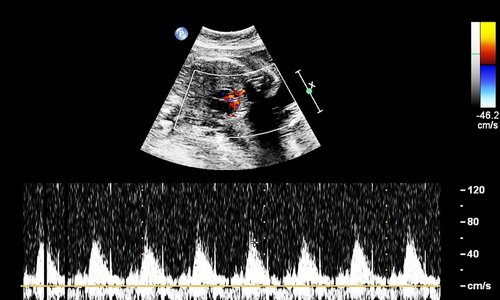

At Vcare Imaging & Diagnostic Center, Kandivali East, we provide specialized Fetal Echocardiography (Fetal Echo) to evaluate the heart of an unborn baby. This advanced ultrasound test helps detect congenital heart defects early, ensuring timely care and treatment planning for both the mother and child.

Fetal Echocardiography is a safe and non-invasive ultrasound examination that focuses on the structure and function of the baby’s heart while in the womb. It is usually recommended between 18 to 24 weeks of pregnancy if there is a risk of heart abnormalities.